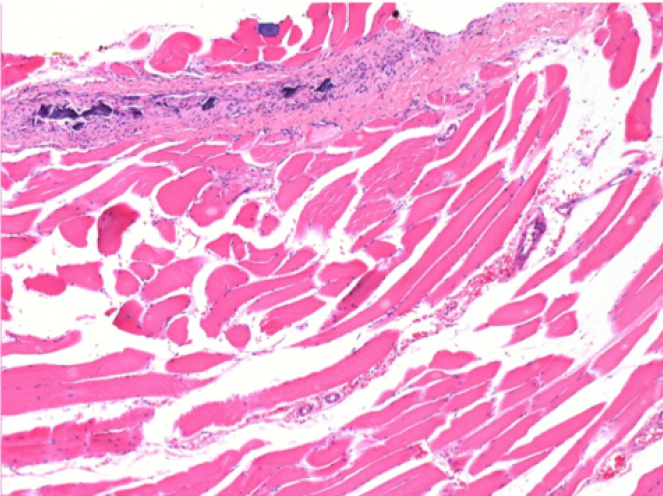

1 month after Endopeel Injection 0.1ml in the right pretibial muscle.

What is seen in black on the pictures is not a necrosis like could imagine some scientifics !

In fact, 4 conclusions have to be taken in consideration